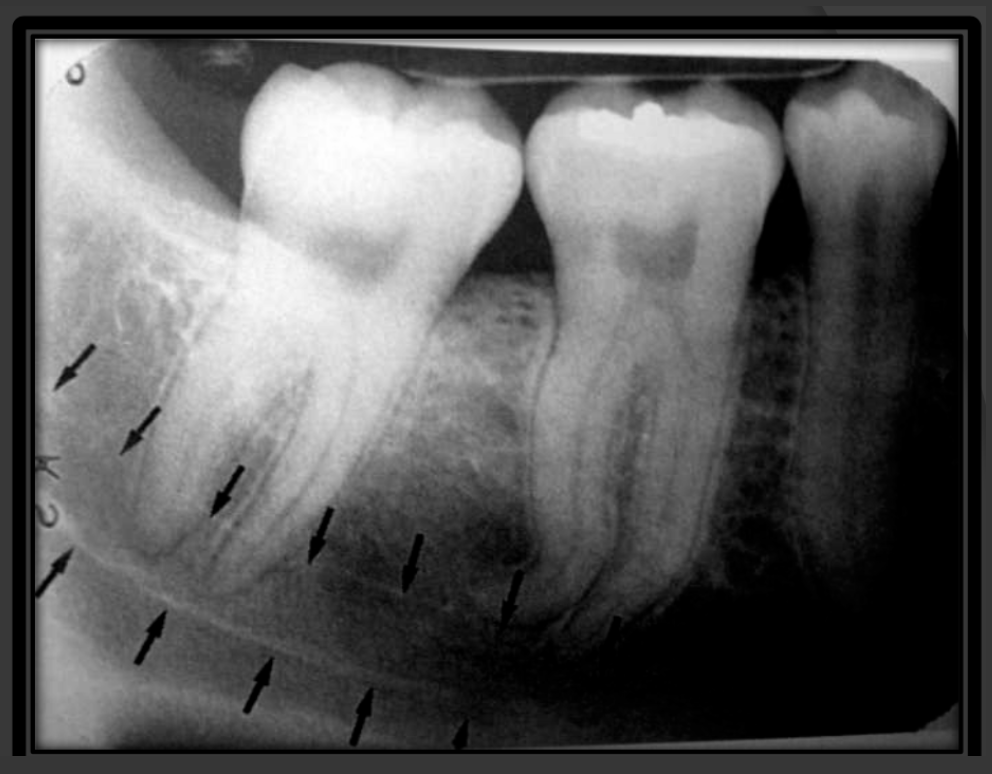

How does the mandibular canal present in a radiograph?

It is a radiolucencent band that follows the contour of the mandible that runs under the teeth.